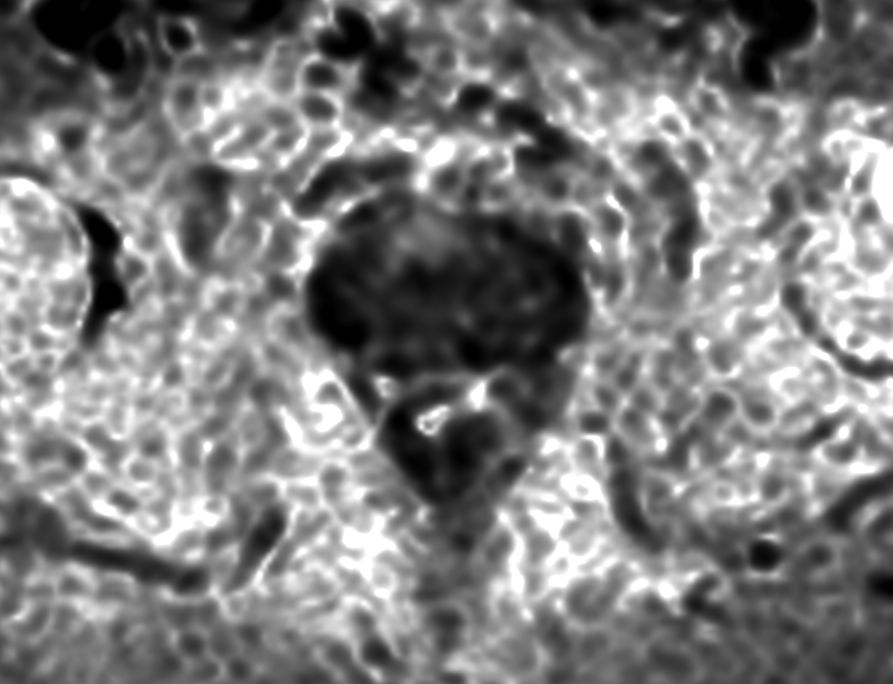

Premium signal-to-noise ratio is achieved via dStream, providing outstanding image resolution.

Resolution